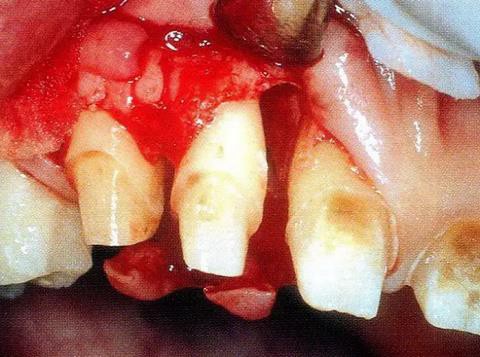

▼圖13-2 將齦溝切開,盡可能保存牙齦組織的情況下做翻瓣形成。確認(rèn)有根面牙結(jié)石。

▼圖13-3 廓清處理結(jié)束的狀態(tài)。觀察到存在圍繞著顎側(cè)根擴展開的骨缺損,之間存在2壁性骨缺損。

▼圖14-2 保存牙齦乳頭的同時進(jìn)行了翻瓣形成,骨缺損部的廓清處理結(jié)束的狀態(tài)。骨缺損形態(tài)是從臨接面向腭側(cè)擴展開來的。